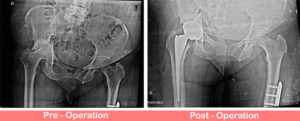

Dysplastic Hip – Right Total Hip Replacement

A 41 years old gentleman presented with pain in the right hip and shortening of right leg by 10 cm. His problem started when he was 10 years of age. Since then the pain in his right hip has been increasing. He was able to manage to walk with a ... Read more..